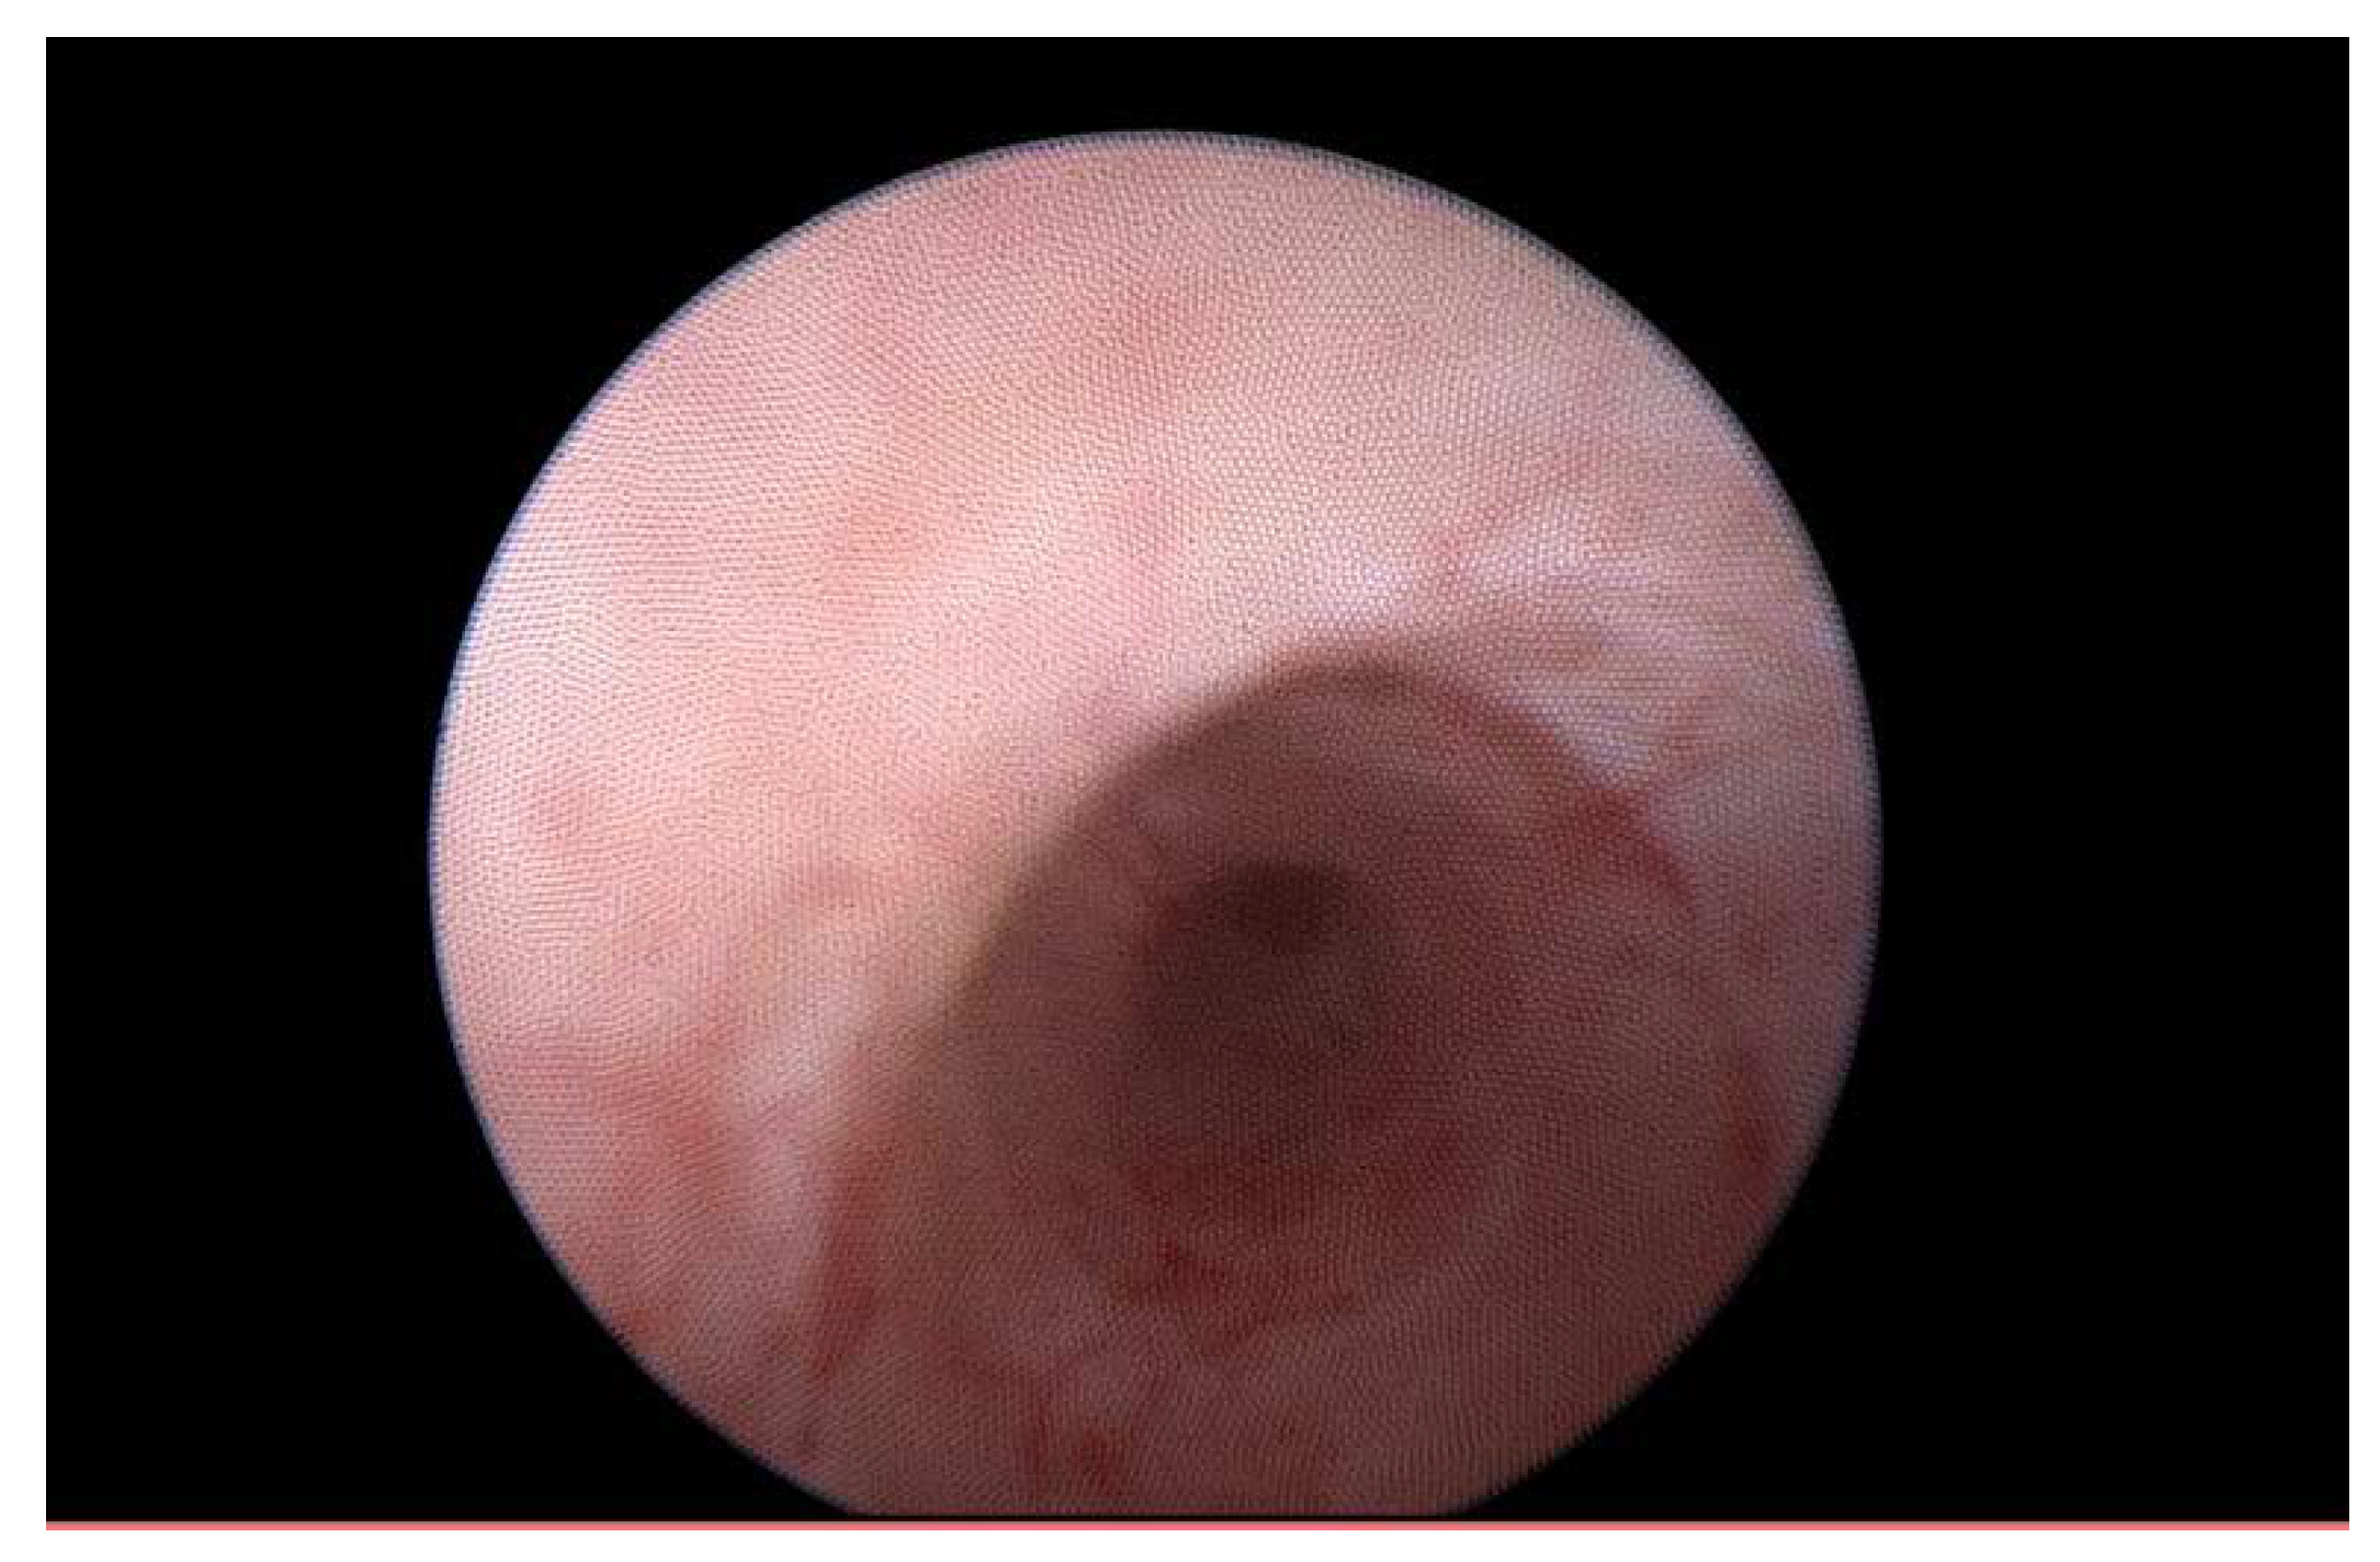

Krukenberg Tumor in Association with Ureteral Stenosis Due to Peritoneal Carcinomatosis from Pulmonary Adenocarcinoma: A Case Report

2. Case Report